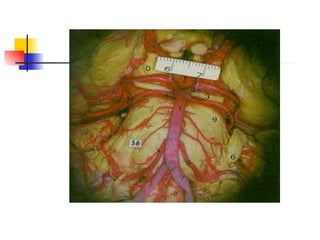

El documento describe la irrigación del cerebro. El tronco braquiocefálico se divide en la subclavia derecha y la carótida primitiva derecha. La carótida primitiva se divide en las carótidas externa e interna. La interna se divide en las arterias cerebrales anterior, media y comunicante posterior. La subclavia se divide en la arteria vertebral, la cual forma el tronco basilar junto con la arteria vertebral opuesta. El tronco basilar emite las arterias cerebrales posteriores, formando así el polígon